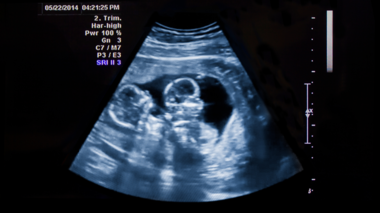

• Twins can grow at different rates, too. Regular ultrasounds make sure they’re both doing okay.